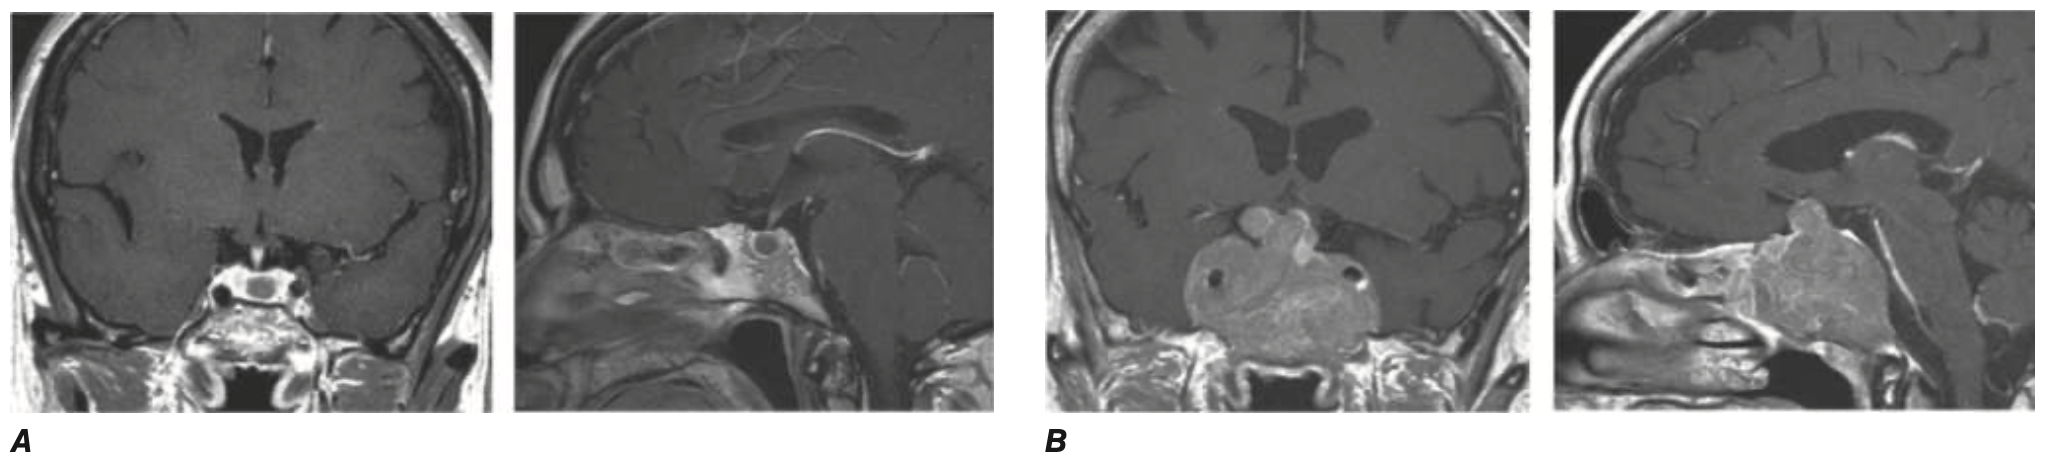

• 영상 검사: MRI evidence for pituitary mass (조영증강 MRI)

• 거대선종 (Macroadenoma): ≥ 10 mm

• 거대선종 (Macroadenoma)

• 4개월 내 MRI 추적 검사 (Repeat MRI within 4 months)